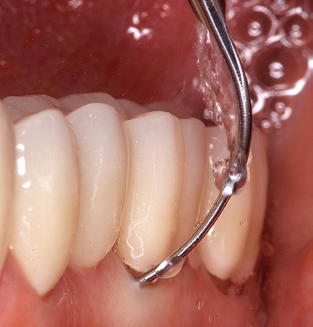

Die gute Ausleuchtung des Arbeitsfeldes stellt eine wesentliche Erleichterung dar. Bei dem von den Autoren genutzten System ist dies gelungen, indem ein 5facher LEDRing in das Handstück integriert wurde. Natürlich werden für dieses System unterschiedliche Arbeitsspitzen für die jeweiligen Indikationsbereiche angeboten. Eine gerade, universell einsetzbare Spitze ist das Basisinstrument zur maschinellen Instrumentierung natürlicher Zähne (Abb. 5a und b). Für schwer zugängliche Bereiche im Seitenzahnbereich werden gebogene Spitzen angeboten, die auch einen Zugang zu freiliegenden Furkationen ermöglichen (Abb. 6).

Nach der maschinellen Reinigung der Zahn und Implantatoberflächen erfolgt eine manuelle Instrumentierung der natürlichen Zahnoberflächen mit konventionellen Handinstrumenten. Bei der manuellen Reinigung ist insbesondere auf einen korrekten Anstellwinkel, eine ausreichende Schärfe, eine gute Abstützung und auf eine von apikal nach koronal gerichtete Arbeitsweise der Kürette zu achten. Zur Nachinstrumentierung der Implantatkonstruktionen sollten entweder Titan oder Carbonküretten verwendet werden (Abb. 8). Ergänzend zum Einsatz von Ultraschallgeräten können in der Erhaltungstherapie auch Pulverstrahlgeräte genutzt werden. Dabei ist jedoch zu berücksichtigen, dass diese Verfahren nicht zum Entfernen harter Beläge geeignet sind und daher die Verwendung von Hand oder Ultraschallinstrumenten nicht komplett ersetzen können. Abschließend erfolgt in jedem Fall eine mechanische Politur der zugänglichen Zahn und Implantatoberflächen mit Polierkelchen und Polierpasten (Abb. 9).